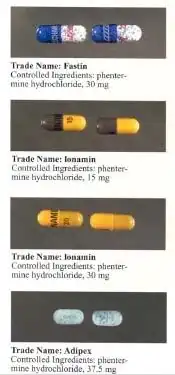

Casos de hipertensão pulmonar fatal e danos na válvula cardíaca associada a produtos farmacêuticos dos anorexígenos levaram à retirada de produtos do mercado na Europa. Este foi o caso do aminorex na década de 1960, e da fenfluramina em 1990.[4] Da mesma forma, a associação do inibidor de apetite fenilpropanolamina relacionadas com acidente vascular cerebral hemorrágico levou a sua retirada do mercado nos Estados Unidos em 2000, e preocupações semelhantes quanto a efedrina resultaram em uma proibição do órgão de controle de drogas americano (FDA) a sua inclusão em suplementos dietéticos, em 2004 (mais tarde um juiz federal anulou esta proibição, em 2005, durante um processo feito pela fabricante de suplementos nutracêuticos). Outro fator importante para a proibição da efedrina foi o seu uso como um precursor na produção de metanfetaminas.[5]